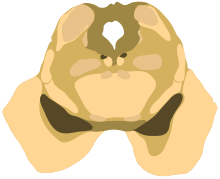

The midbrain is usually sectioned at the level of the superior and inferior colliculi.

- A horizontal (transverse) cross-section at the level of the inferior colliculus still shows the substantia nigra. Also apparent are the trochlear nerve nucleus, and the decussation of the superior cerebellar peduncles.[8]

- Both sections will show the cerebral aqueduct, which connects the third and fourth ventricle and the periaqueductal gray.[9]